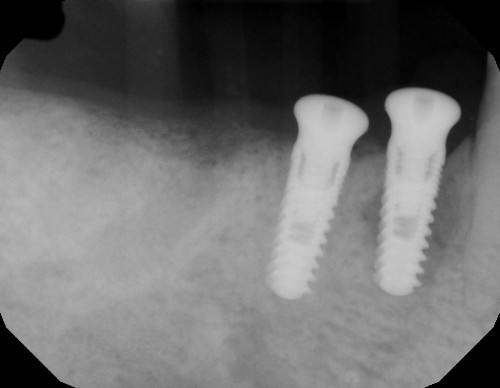

Ossification is a complex and sometimes unpredictable process. I think 10 weeks is a too soon for implant placement since the extraction socket hasn’t fully calcified and you still have spongy bone inside the socket and psuedoperiosteum on the occlusal of the socket. I noticed radiographically i can see still see the socket. I usually enter and place implant at 4 months minimum post extraction, ideally 6 months, when radiographically the socket is mostly radiopaque indicating more calcification and ridge remodeled consistent to final dimensions.

I also noticed at implant placement i see 2 occlusal defects mesial and distal of the implant (most likely indicating mesial and distal root of previously extraction). which indicated the ridge is not fully ossified or calcified. i wonder if during osteotomy you felt soft bone instead of the usually hard mandibular bone. i think at implant placement you should have grafted. the occlusal is kind of flat, as if you did some occlusal reduction of some kind.

Your implant position is impeccable. good depth and orientation in the ridge.